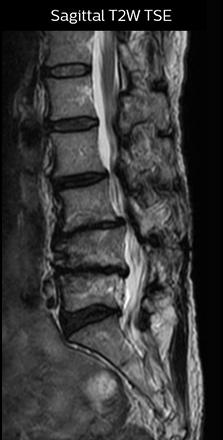

The key concept in MR neurography, Dr. Yabuki stresses, is the ability to directly visualize spinal nerves, versus inferring the presence of pathology indirectly. “Before NerveVIEW, we estimated compression of the nerve by looking for the presence or absence of fat signal on other MR images,” he says.

“For example, in sagittal images, when the presence of fat is observed in the intervertebral foramen, it suggests that there is a margin around the nerve. Similarly, the absence of fat indicates that the nerve is being compressed. So, we used to deduce nerve compression indirectly. With NerveVIEW, however, we can observe the condition of the nerves directly, regardless of the presence or absence of fat. We always prefer such direct observation of anatomy over having to make an inference about it.”